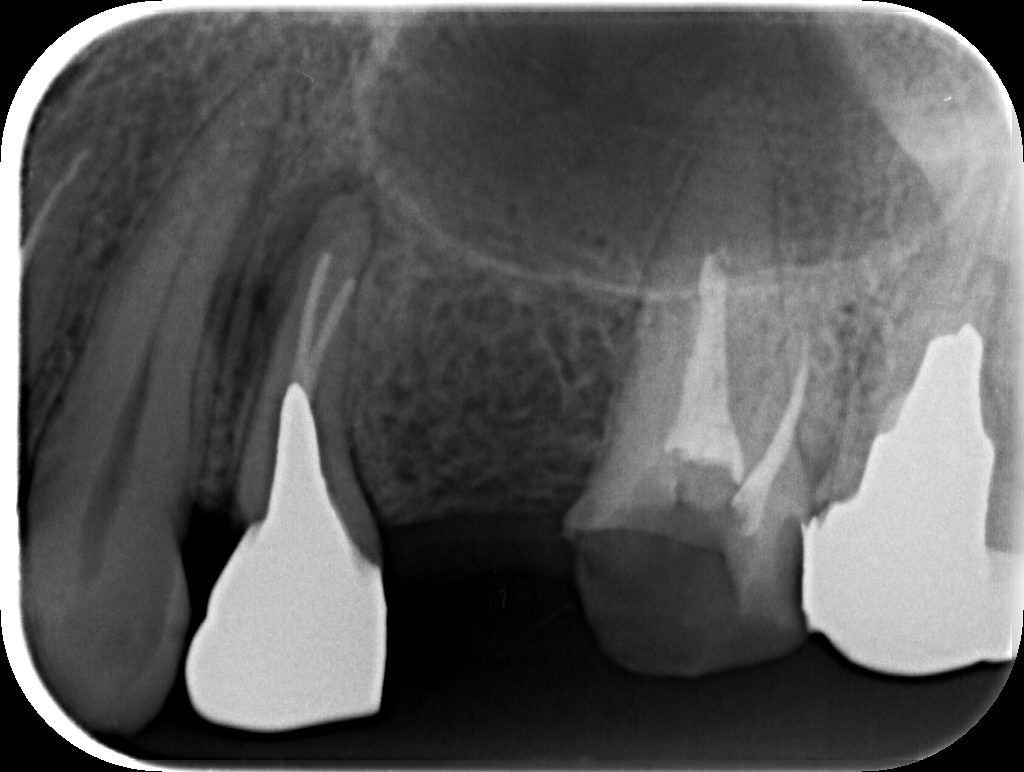

before

2007年

開業して間もない時来院。すでに神経の処置がしてある歯が目立つ。ただ幸いにも上下左右の犬歯はご自身の歯で、処置も最低限で済んでいる。

2008年

左上ブリッジが破折。左上第一小臼歯の歯根破折。第一大臼歯はなんとか再補綴可能。小臼歯部を2本のインプラントで修復予定。